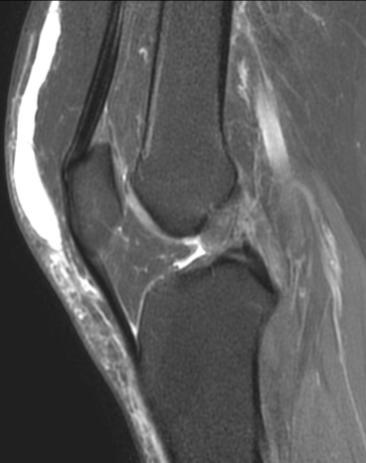

3. MRI检查:MRI在神经系统疾病的诊断中优势显著,对于脑肿瘤、脑梗死、脊髓病变等的诊断准确性较高。例如,对于一些早期的脑肿瘤,MRI能够更清晰地显示肿瘤的位置、大小、范围以及与周围组织的关系,有助于制定治疗方案。在关节疾病方面,MRI可以清晰地显示关节软骨、半月板、韧带等软组织的损伤情况,对于膝关节半月板损伤、交叉韧带断裂、肩关节肩袖损伤等疾病的诊断具有重要价值。此外,MRI在乳腺疾病、盆腔疾病等方面也有广泛的应用。

脑肿瘤T1WI+C、右膝外侧半月板撕裂、右侧膝前交叉韧带断裂、右侧肩袖损伤